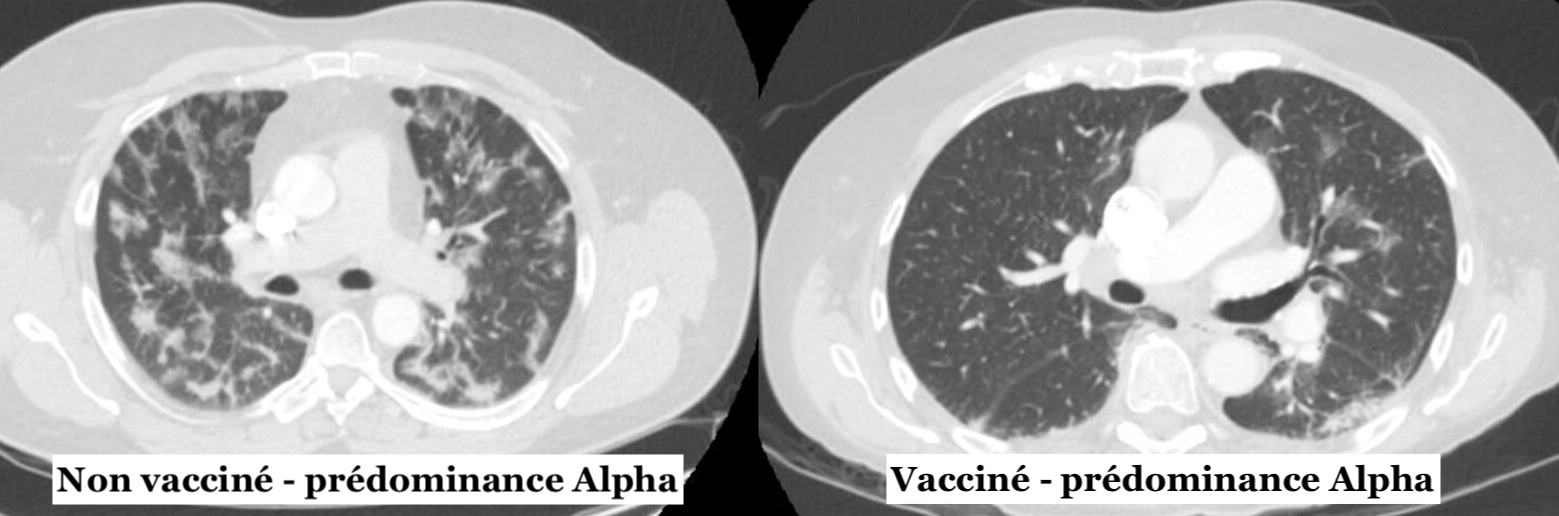

Dans l'ensemble, le taux de vrais positifs COVID typiques était plus élevé chez les sujets non vaccinés [73 %) par rapport aux sujets entièrement vaccinés (41 %). Les taux de vrais positifs variaient également avec les nouveaux variants. Par rapport aux sujets entièrement vaccinés, les sujets non vaccinés avaient des taux de vrais positifs plus élevés pendant la prédominance du variant Alpha (67 %) contre 11 %, alors que pendant la prédominance du variant Delta les taux étaient de 88 % versus 47 %. Par ailleurs, il n’a pas été détecté de différence significative de taux de vrais positifs entre les groupes de statut vaccinal pendant la prédominance du variant Omicron (87 % contre 79 %).